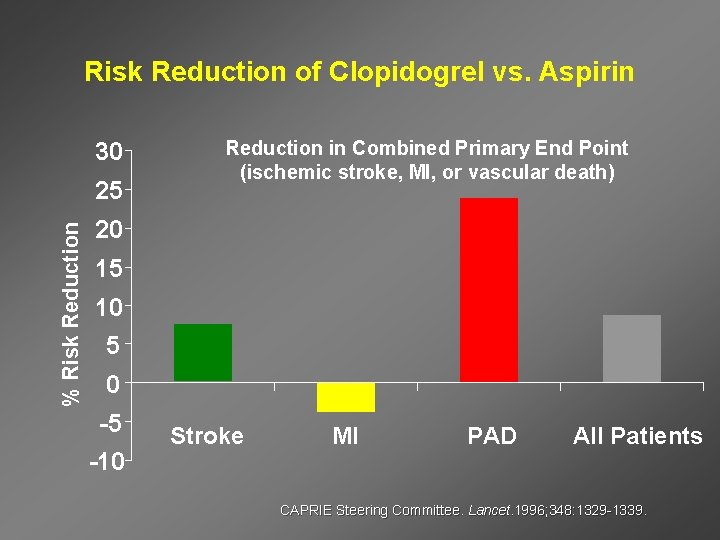

Risk Reduction of Clopidogrel vs. Aspirin 30 % Risk Reduction 25 Reduction in Combined Primary End Point (ischemic stroke, MI, or vascular death) 20 15 10 5 0 -5 -10 Stroke MI PAD All Patients CAPRIE Steering Committee. Lancet. 1996; 348: 1329 -1339.